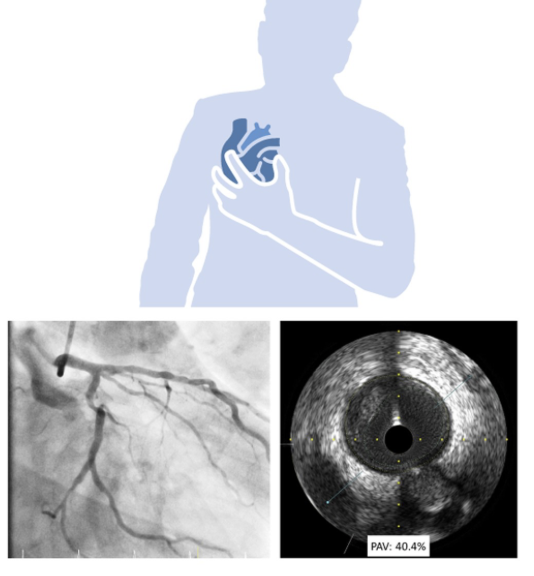

Profesor. Licenciado en Fisioterapia. Escritor. Especialista en educación universitaria. Fisioterapeuta cardiovascular. Coordinador del Sistema Súper Viviente.